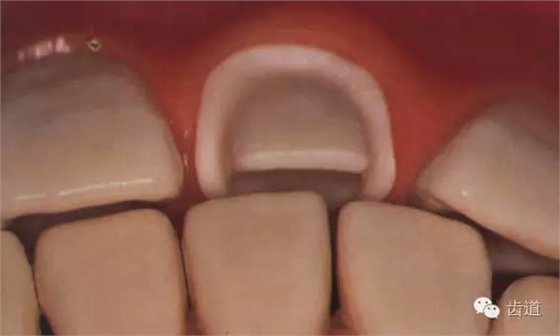

1、鄰面預(yù)備:兩鄰面相互平行或聚合2-5°

2、舌面預(yù)備

(1)舌隆突-切緣預(yù)備出修復(fù)體所需的間隙均勻磨除

(2)舌隆突-齦緣去除倒凹,與牙體長(zhǎng)軸平行或內(nèi)聚2°~5°,并在舌側(cè)形成0.5mm寬的凹形肩臺(tái)